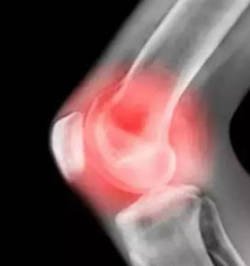

(图:张先生在治疗前膝关节肿胀)

【来院检查】

来到医院后,杜爱华主任为张老做了检查后,初步诊断为风湿性关节炎,为了诊断和治疗的准确性,杜爱华主任建议张老先进行风湿性关节炎的常规检查,在经过详细地检查后,报告显示出张老师双膝关节红肿,皮温升高,关节活动明显受限,浮髌试验阳性,侧方挤压试验阳性抽屉试验阴性,研磨试验阴性,麦氏征阴性,X线检查有软组织肿胀,ESR↑,抗"O"(+)。C-反应蛋白24.15mg/L,血沉 85mm/h,血小板 531 ×109/L 。属于风湿性关节炎中晚期。杜爱华主任考虑到张老的年龄和身体状况,决定采用安全高效的净骨疗法体系为张老进行治疗。

(图:张先生在治疗后膝关节明显消肿)